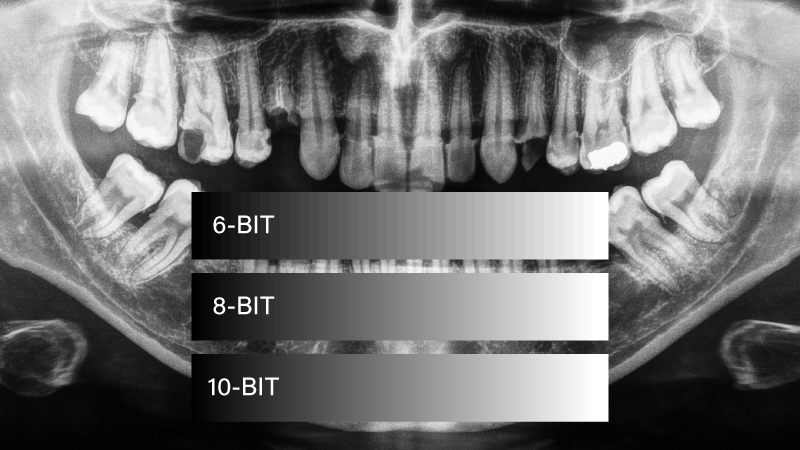

Even if a monitor supports DICOM, its grayscale rendering and bit depth must also be optimized. Subtle variations in grayscale intensity allow dentists to detect fine details in bone structures, fractures, and root conditions.

However, some monitors with DICOM mode may still lack adequate grayscale accuracy due to insufficient bit depth. Many consumer-grade monitors use 6-bit + FRC (Frame Rate Control) instead of true 8-bit grayscale depth, leading to:

Poor grayscale differentiation, making it harder to detect slight variations in bone density.

Color banding and inaccurate contrast, which can obscure fine details in radiographic images.

6-bit + FRC (Simulated 8-bit) – Can produce artificial grayscale transitions, leading to potential image distortion and misinterpretation.

True 8-bit grayscale and above – Provides smoother grayscale gradations, ensuring clear and precise visualization of X-ray and CBCT images.

In contrast, DICOM Part 14-compliant dental imaging displays with true 8-bit grayscale depth ensure:

• Accurate grayscale rendering, preserving subtle details in radiographic images.

• Consistent brightness and contrast, reducing the risk of misinterpretation in diagnosis.